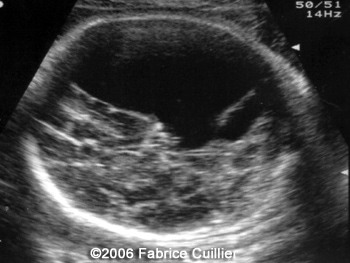

The following images are obtained in a 3rd trimester fetus:

The final diagnosis was: Arachnoid cyst